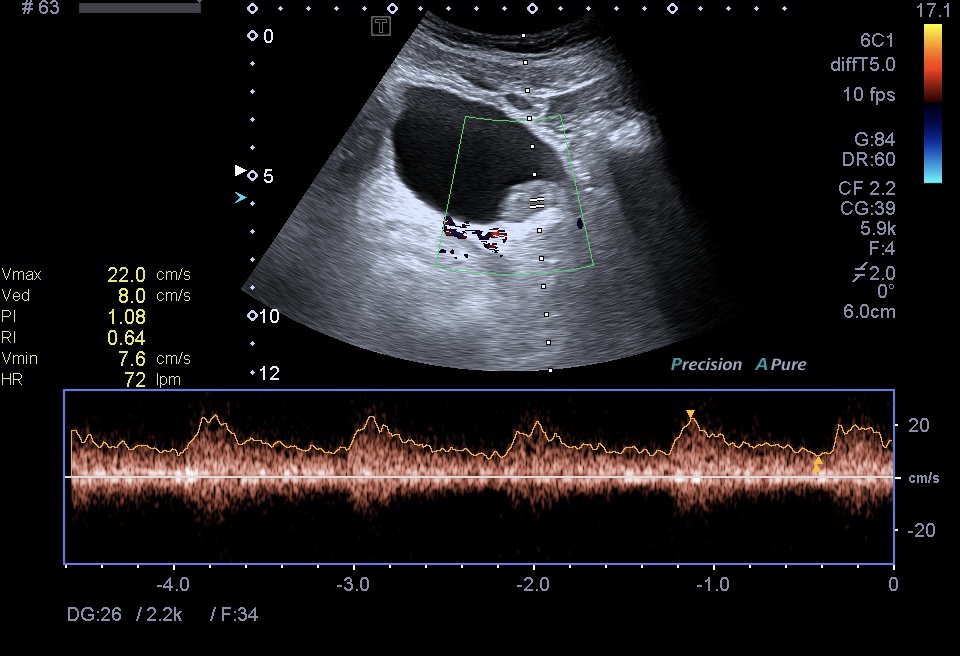

Al realizar una ecografía reno vesical, los hallazgos ecográficos típicos del urotelioma incluyen la visualización de una masa sólida en la vejiga.

Esta masa puede presentar una apariencia heterogénea, con áreas hipoecoicas (menos ecogénicas) y áreas hiperecoicas (más ecogénicas) en relación con el tejido circundante. Además, puede observarse un crecimiento intraluminal, lo que significa que la masa se proyecta hacia el interior de la vejiga.

- Estructura interna: La estructura interna del urotelioma puede ser heterogénea debido a la presencia de áreas de necrosis o hemorragia. Estas áreas pueden ser identificadas por su apariencia hipoecoica o hiperecoica respectivamente.También calcificiones…como es el caso que nos ocupa hoy.

- Vascularización: La evaluación de la vascularización del urotelioma mediante el registro Doppler es crucial. La presencia de flujo sanguíneo dentro de la masa tumoral, representado por colores en el Doppler, sugiere un mayor riesgo de malignidad.

La vascularización es un hallazgo considerado línea roja.

Se recomienda el uso de Doppler Power para detectar vascularización lenta.